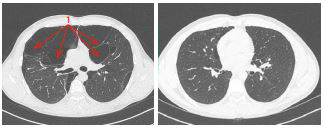

Fällt die Sauerstoffsättigung in Ruhe und unter Belastung unter 90%, ist eine Sauerstofftherapie angezeigt, die durch einen mobilen und/oder stationären Sauerstoffkonzentrator über eine Nasenbrille verabreicht wird. Beim fortgeschrittenen Lungenemphysem kommt nach Ausschöpfen der konservativen Therapien auch eine bronchoskopische oder operative Lungenvolumenreduktion (LVRS) in Frage, bei der die überblähten Lungenteile entfernt werden (vgl. Abb. 3). Die Auswahl der Patienten erfolgt bei uns an einem interdisziplinären Emphysemboard.

Emphysemblase

Abb. 3: Lunge mit grossen Emphysemblasen (1) vor einer LVRS (links)

und danach (rechts)